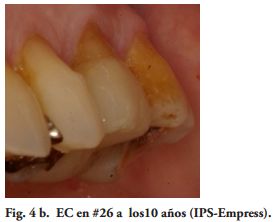

Al momento del examen, 10 (90.9%) EC estaban en función en 10 pacientes. Un molar 26, restaurado con EC, se perdió por enfermedad periodontal después de 12 años y 9 meses en función. Ninguna restauración se desprendió, no hubo recidiva de caries y al examen radiográfico no se observaron lesiones patológicas en los 10 DPET en función (Figs. 1a,1d; 2c; 3c,3d; 4c).

Dos pequeñas fracturas en crestas marginales distales fueron pulidas, sin afectar la restauración. El Éxito Clínico, relacionado a la calidad de las restauraciones, fue Excelente, 5 (50%), Bueno, 4 (40%) y Sobrevida Funcional, 1(10%) (Tabla 2).

Por su parte, varios estudios clínicos, concluyeron que el remanente coronario es el factor más importante en el éxito clínico del DET (18-21). Por lo tanto, un criterio conservador es esencial en la preparación dentaria para un EC. Toda la superficie oclusal debe ser cubierta por la restauración, teniendo en cuenta la función oclusal del paciente. Los onlays transmiten fundamentalmente, fuerzas compresivas en la interfase adhesiva restauración - diente, mejorando el comportamiento biomecánico (22-24). Para este procedimiento restaurador fue sugerido un espesor oclusal de 3 mm. (25) y aumentando el mismo la resistencia a la fractura sería más alta (26). Además. si las paredes vestibular y/o palatina o lingual, tienen un espesor mayor de 2.0 mm., un chamfer de 1.2 mm. en oclusal de estas paredes, podrían tener un efecto zuncho o abrazadera, aumentando la resistencia a la fractura de los dientes y la retención de la restauración (Figs. 3a, 4a).

Los autores de este trabajo, consideran que extender la preparación a la cara vestibular está condicionada por requerimientos estéticos o reducidas dimensiones de la misma. En esta situación clínica (Fig. 4a), una reducción axial de 1.2 mm. de la pared vestibular fue suficiente. En vestibular, distal y palatino, el borde cavo de la preparación se definió en forma de chamfer. Estos criterios no concuerdan con la reducción total de la corona dentaria, propuesta por Fages y Benassar (9).

Mientras, en estudios clínicos y de laboratorio, los cementos resinosos de polimerización química y dual, tuvieron un mejor comportamiento que los fotopolimerizables y los de autograbado (38-44). Sin embargo, utilizando unidades de curado LED de alta potencia y aumentando el tiempo de exposición, a través de materiales cerámicos con diferentes espesores, recientes investigaciones de laboratorio han encontrado mayor grado de conversión y después de 24 horas, mayores valores de microdureza, en cementos resinosos fotopolimerizables y duales (45,46). Por lo tanto, los procedimientos clínicos y los cementos utilizados, pudieron haber influido en el Éxito Clínico obtenido (90%) (Figs. 1c, 2b, 3b, 4b).